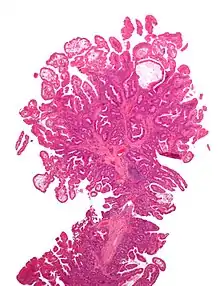

| Type | Risk of containing malignant cells | Histopathology | Image | |

| Hyperplastic polyp | 0% | No dysplasia.[10]

|

![]() | |

| Tubular adenoma | 2% at 1.5 cm[12] | Low to high grade dysplasia[13] | Over 75% of volume has tubular appearance.[14] | ![]() |